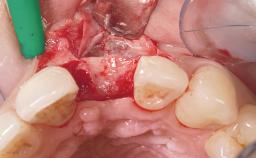

A 30-year-old female patient was referred to the office for the treatment of tooth 11. Her chief concern at the initial visit was to inquire, “Why is my tooth pink?” Upon clinical examination, it was determined that tooth 11 had a previous history of trauma and that the clinical crown had become noticeably pink in color as a result of internal resorption. This diagnosis was confirmed radiographically, indicating a large radiolucency involving the central and distal portions of the clinical crown. It was determined that restoration of this tooth was not possible, and that extraction was indicated. The presence of a mid-line diastema, which the patient wanted to reproduce, directed the treatment plan for tooth replacement utilizing a dental implant.

Placement Protocol Immediate implant placement

Tooth Site Maxillary incisor or canine

Socket Morphology Single-root socket

Socket Integrity Sufficient, with intact bone walls